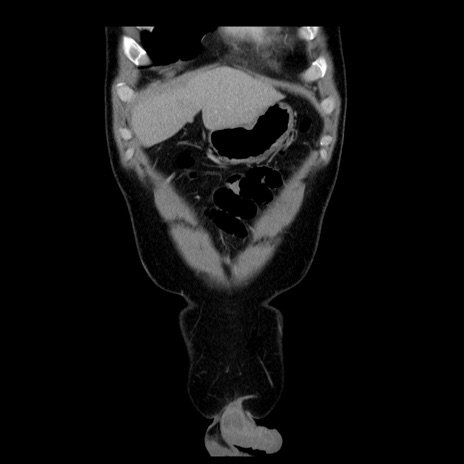

横断像

【症例】30歳代男性

【主訴】腹痛、嘔吐

【現病歴】昨晩から突然の腹痛あり、その後嘔吐、軟便も出現。腹痛が改善しないため救急搬送となる。2日前にしめ鯖の食事歴あり。

【身体所見】意識清明、苦悶様、BP 135/90mmHg、BT 35.7℃、腹部:平坦、やや硬、心窩部〜臍部に自発痛、圧痛あり、筋性防御+、反跳痛-

【データ】WBC 8100、CRP 0.57